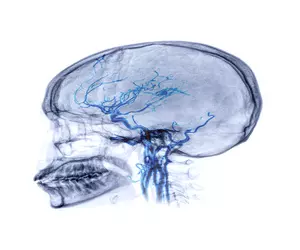

뇌졸중은 뇌혈관이 막히거나 터져 뇌세포가 손상되는 급성 질환입니다. 뇌는 우리 몸의 모든 기능을 조절하는 중요한 기관이기 때문에 뇌졸중은 사망률과 장애율이 매우 높은 질환입니다.

하지만, 뇌졸중은 조기 발견과 빠른 치료로 치명적인 결과를 막을 수 있습니다. 뇌졸중에는 7가지 전조 증상이 나타나며, 이 증상을 놓치지 않고 즉각적인 치료를 받는 것이 중요합니다.